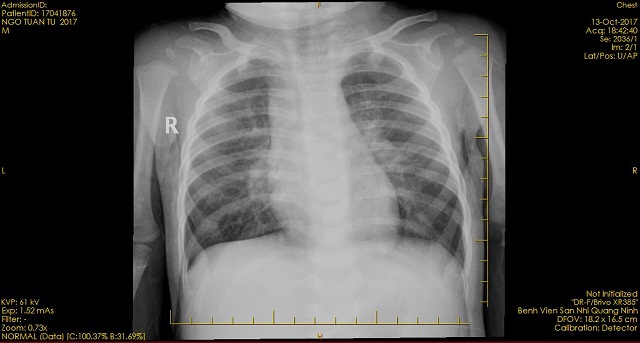

Hình ảnh phim chụp của bệnh nhi sau khi đưa đến viện.